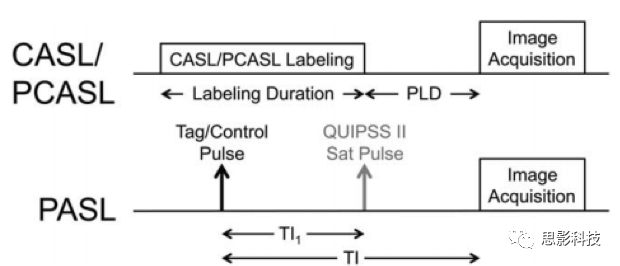

对于PCASL,由两个时间点定义了标记脉冲序列的时间,开始和结束,它们的间隔时间为1500~2000ms。此脉冲序列结束到图像采集之间的时间称为PLD。对于PASL,由于标记脉冲几乎是瞬时的,所以标记脉冲的时序特征为单一时间点。从应用该脉冲到图像采集的时间称为翻转时间(TI)。因为PLD是指在PCASL中已标记厚块的末端离开标记平面的时间,因此在PASL中的类似时间是已标记厚块的末端通过标记层远端的时间。在PASL中,这个时间通常是未知的,因为在PASL中标记区间的时间宽度是不受控制的。通过前面提到的QUIPSS-II进行修改,厚块的宽度被控制,称为TI1。PCASL中的PLD类似于(TI-TI1)的量化,如图3所示。

单PLD采集方法

使用PCASL进行CBF量化,理想情况是将PLD设置为刚好大于对象中存在的动脉传输时间的最长值。在这些条件下,整个标记的大剂量血液在图像采集之前被传送到组织,并且CBF测量将因不完全的传送而无畸变。由于ASL信号在标记后随时间常数T1衰减,因此就信噪比而言,代价太高,以至于在选择PLD时过于保守,研究者要求在任何情况下都要严格保证PLD比动脉转移时间长。在健康灰质中,根据标注定位的不同,其动脉传输时间大约在500到1500ms之间。但是在某些脑血管疾病以及深部灰质中,动脉传输时间则会大于2000ms。因此PLD的选择根据对信噪比的要求以及扫描范围的大小,以保证大脑CBF的精确测量为前提作折衷选择。而且也要意识到ASL信号较弱的区域可能不单单是脑血流量低的结果,而有可能是较低的脑血流与不寻常的长动脉传输时间共同作用导致的。一些情况下标注过的自旋血液滞留在动脉之中也会到导致动脉传输时间的延长。而这种情况与人的年龄关系较大,越发高龄的被试中这种情况越发常见。因此PLD的选择也需要根据被试年龄作适当调整。在表1中列举了推荐的PLD数值,其中针对于成年患者的临床使用可用2000ms的PLD,该参数相对独立于年龄,且在各种各样的未知的疾病中也同样适用。

基于上述分析,使用单个PLD的PCASL是可以稳定直接采集脑血流的方法,因此也是在临床应用上推荐的标准方案。而待QUIPSS-Ⅱ修正的PASL类似于PCASL可以很好地确定标注后的持续时间,并允许在单个TI的条件下量化CBF。但是由于PASL信噪比过差,我们推荐在PCASL无法使用的情况下使用PASL。对于带QUIPSS-Ⅱ修正的PASL推荐TI应该设置在800ms,具体的设置参数可参考表1。需要注意的是 PCASL中的PLD与PASL中TI的定义是类似的。这有效地导致PASL的TI比PCASL短800ms。虽然这并不理想,因为它增加了不完全标记血液输送到PASL成像区域的可能性,但它也增加了信噪比,被认为是弥补PASL固有的低信噪比的必要权衡。另外通过降低图像的分辨率来保证信噪比也是一种可行方法,但是其还未在临床做过测试。